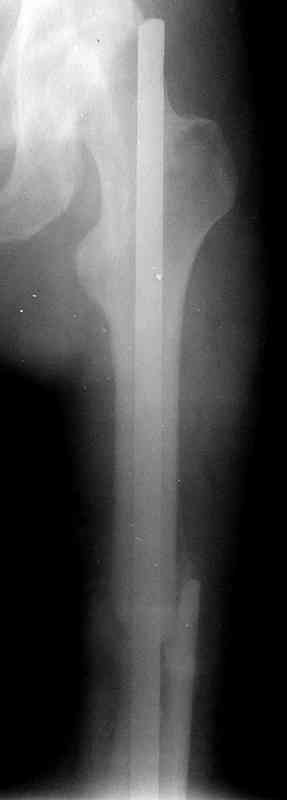

Больной А., 28 лет, поступил в НИИ им. Н.В. Склифосовского 22.12.99 после падения на улице. Жалобы на боли в области левого тазобедренного сустава и левом бедре. Из анамнеза следовало, что 20.06 во время прыжка с парашютом у него возник закрытый оскольчатый перелом средней трети левой бедренной кости со смещением отломков, по поводу чего в одной из ЦРБ Московской области через 3 дня после травмы был произведен открытый интрамедуллярный остеосинтез штифтом типа Кюнчера.

Послеоперационное течение было гладким. Больной ходил при помощи костылей с дозированной нагрузкой на оперированную конечность.При осмотре в НИИ им. Н.В. Склифосовского через 6 месяцев после травмы:

левое бедро и левый коленный сустав несколько увеличены в объеме, отечны, пальпаторно определяется болезненность в средней трети бедра;

по его наружной поверхности послеоперационный рубец - рана зажила первичным натяжением. При измерении длины бедер обнаружено укорочение левого бедра на 4,5 см. На рентгенограммах этого бедра: ось конечности правильная, отмечается захождение основных костных фрагментов по длине, проксимальный конец штифта выступает слишком медиально и высоко относительно большого вертела, периостальная мозоль незначительна.22.12 - через 6 месяцев после операции, произведенной в ЦРБ, нами по поводу замедленно консолидирующего перелома левой бедренной кости с ее абсолютным укорочением под наркозом произведена операция: удаление штифта, закрытый блокирующий интрамедуллярный остеосинтез перелома левого бедра штифтом без рассверливания (UFN) длиной 40 см, диаметром 10 мм с блокированием только проксимальных отверстий (динамический остеосинтез). Наложен аппарат Илизарова на 4 полукольцах с целью удлинения укороченного бедра. Послеоперационное течение без особенностей. Ежедневно осуществляли дистракцию отломков на 1 мм. Через 3 недели после операции больной выпи-сан на амбулаторное лечение с продолжением дистракции отломков. В течение 1,5

месяцев дистракции укорочение левого бедра удалось полностью устранить. 22.02.00, т.е. через 2 месяца после повторного остеосинтеза, больному произведено дистальное блокирование штифта двумя винтами и демонтирован аппарат Илизарова. В течение 2 недель после операции больной ходил с помощью костылей, потом 2 недели с тростью. Опороспособность и функция оперированной конечности полностью восстановились через 4 недели после операции.

Фиксаторы удалены через 12 месяцев после операции, выполненной по поводу замедленной консолидации перелома бедра с его укорочением.